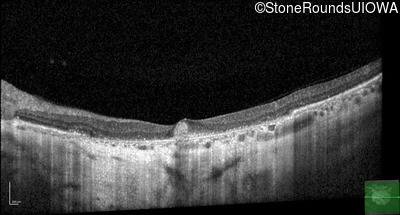

Optical Coherence Tomography - Right - 5/250

Exemplar / OCT Stack